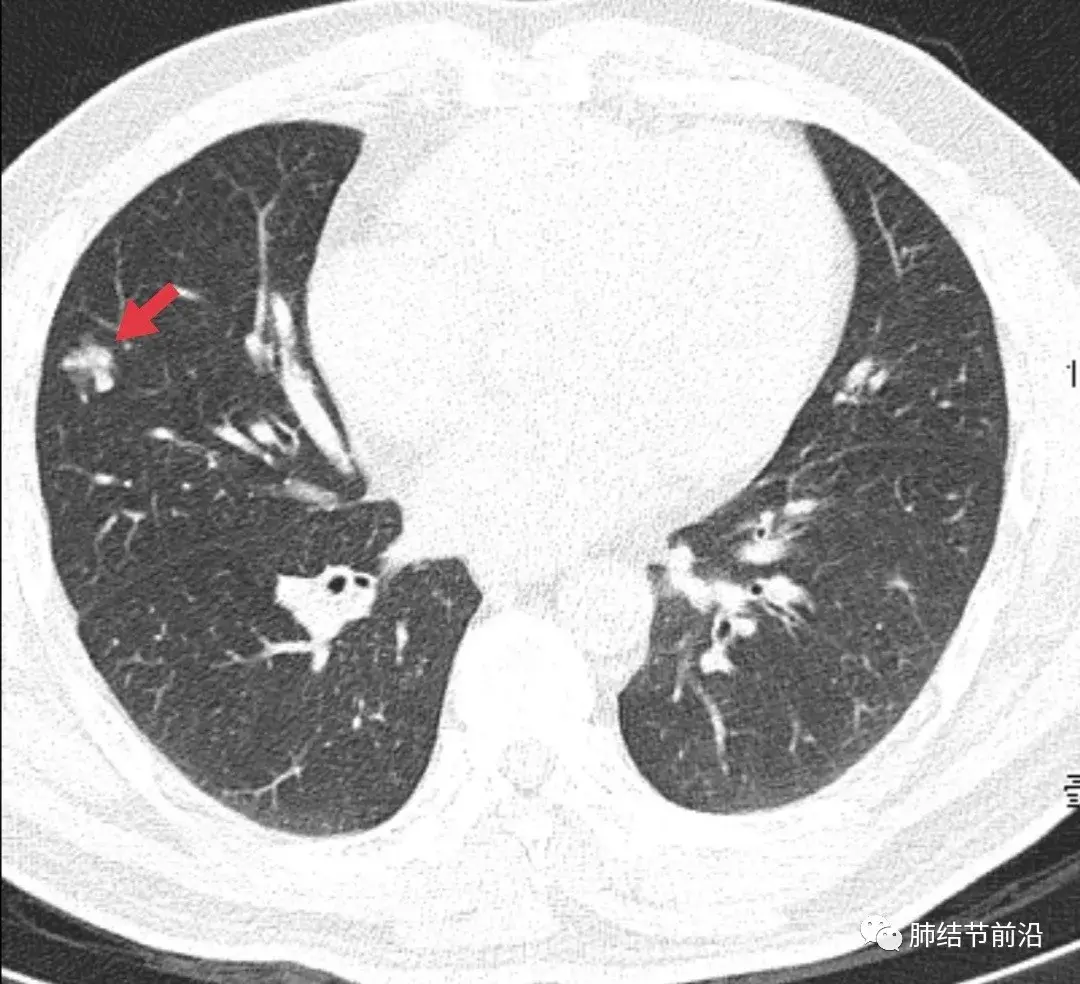

肺腺癌并多发结节,术后2年8个月,磨玻璃结节增大

各种各样的肺腺癌

肺腺癌CT

肺腺癌CT图片

浸润性肺腺癌